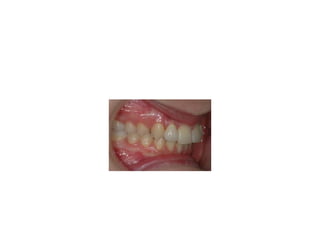

pre-op